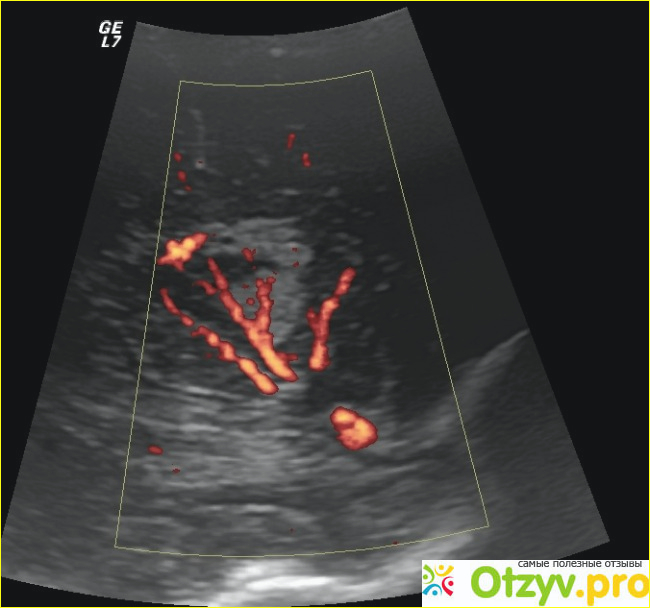

В настоящее время, болезни желудка и кишечника очень распространены. Так как продукты питания сейчас не очень хорошего качества, это я так думаю. А вот в клинико-диагностическом центре Вита Лонга можно сделать УЗИ кишечника и желудка на новом современном оборудование.